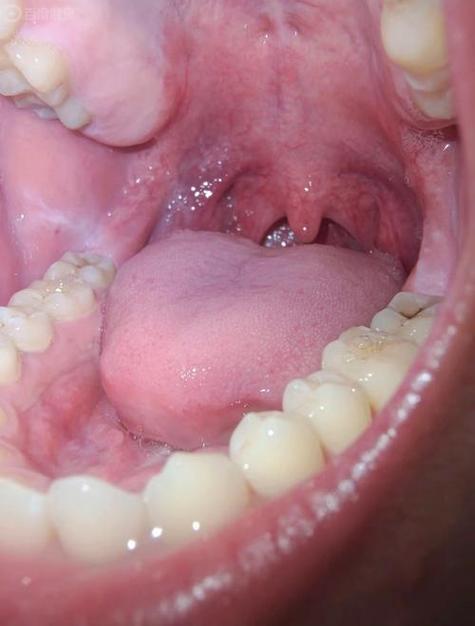

口腔扁平苔藓诱因有哪些?

口腔扁平苔藓的确切病因目前尚不完全明确,医学界普遍认为它不是由单一原因引起的,而是多种因素共同作用、相互影响导致的慢性炎症性疾病,可以把它理解为一个“导火索”点燃了“易燃体质”,最终引发了疾病。

(图片来源网络,侵删)

- 核心观点:口腔扁平苔藓是一种由T淋巴细胞介导的自身免疫性疾病,就是身体的免疫系统“敌我不分”,错误地攻击了口腔黏膜中正常的细胞(特别是基底层的角质形成细胞),导致细胞损伤、凋亡,从而出现那些典型的白色花纹、糜烂等症状。